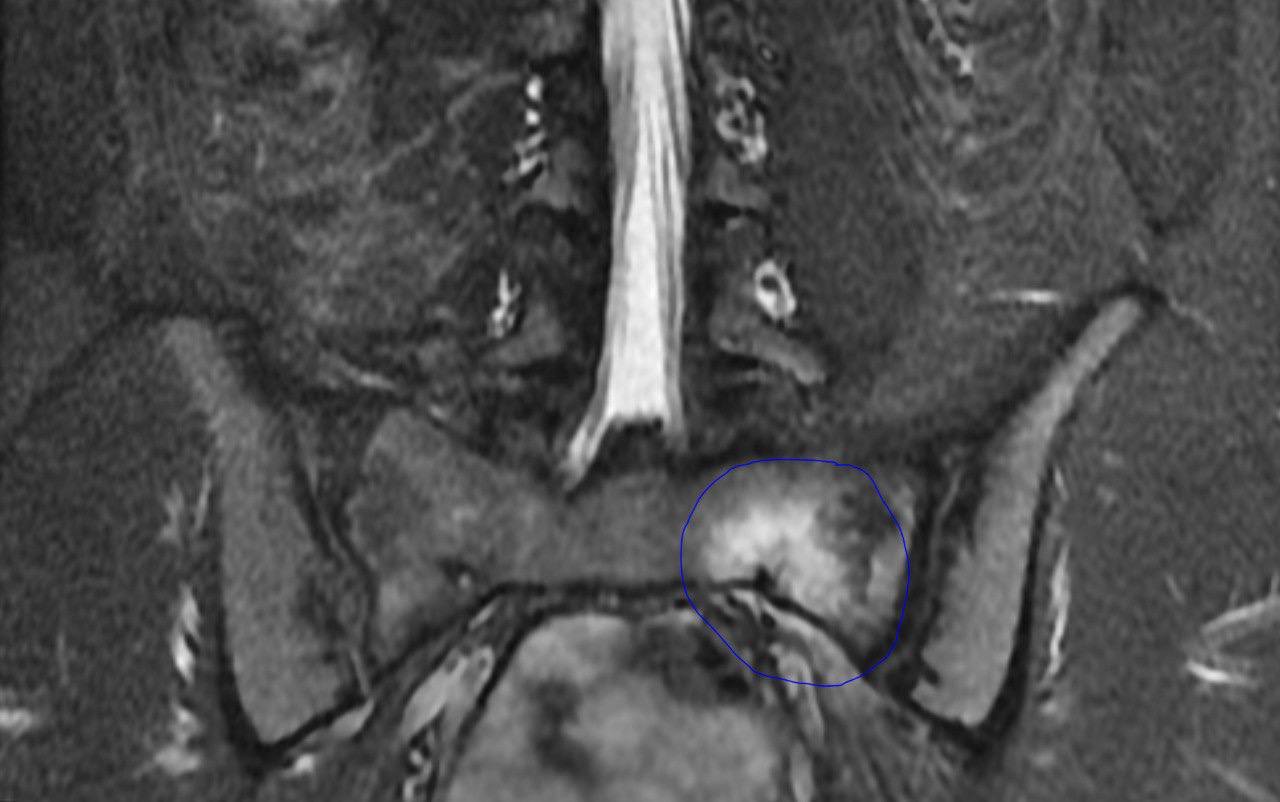

На МРТ: признаков компрессии корешков не выявлено, однако были обнаружены изменения в крестце, попавшем в зону исследования:

• отёк костного мозга,

• гипоинтенсивная неровная линейная структура, проходящая в центре зоны отёка.

Заключение: стресс-перелом левой половины тела S1 позвонка.

На изображении:

• синим - зона отёка костного мозга

• красным - линия перелома